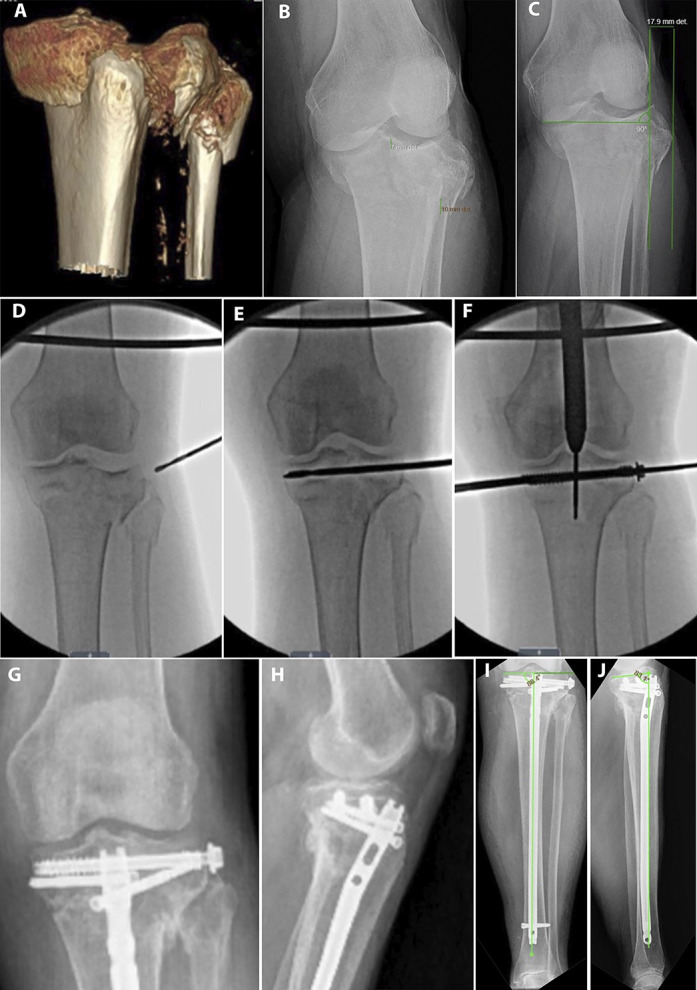

目的:比较髌上髓内钉(IMN)与双钢板切开复位内固定(ORIF)治疗双髁胫骨平台骨折(OTA/ ao41 - c2 /C3)的关节复位和对准维持效果。设计:回顾性队列研究。环境:单一一级学术创伤中心。患者/参与者:2012年7月至2022年7月期间接受治疗的58名成年人(28名IMN, 30名ORIF);各组根据年龄、体重指数和骨折类型进行匹配。干预措施:与标准开放入路行双钢板ORIF相比,采用≥1枚独立拉力螺钉的半扩展髌上IMN。主要结果测量:关节线凹陷、髁突加宽、胫骨内侧近端角(MPTA)和胫骨后部近端角(PPTA)愈合(12个月)。结果:ORIF队列的初始位移更大(关节线8.2 mm vs 5.6 mm, P = 0.014;扩大7.2 mm vs 5.8 mm, P = 0.150)。在12个月时,愈合的宽度(0.6 mm IMN vs 1.0 mm ORIF, P = 0.856),愈合的凹陷(2.0 mm vs 1.1 mm, P = 0.991), MPTA(89.9°vs 89.6°,P = 0.699)和PPTA(11.3°vs 9.8°,P = 0.078)没有差异。没有发生需要修正的二次复位损失。结论:髌上IMN维持了OTA/AO C1、C2和某些C3骨折愈合后的关节线移位、髁突加宽、MPTA和PPTA。手术恢复和维持MPTA和PPTA。该技术在胫骨平台骨折的ORIF使软组织包膜处于危险中或在其他情况下首选髓内植入物的情况下可能有用。证据等级:三级。

Objectives: Compare maintenance of articular reduction and alignment in bicondylar tibial plateau fractures (OTA/AO 41-C2/C3) treated with suprapatellar intramedullary nailing (IMN) versus dual-plate open reduction and internal fixation (ORIF).

Intervention: Semiextended suprapatellar IMN with ≥1 independent lag screw compared with dual-plate ORIF performed through standard open approaches.

Main outcome measurements: Joint-line depression, condylar widening, medial proximal tibial angle (MPTA), and posterior proximal tibial angle (PPTA) at union (12 months).

Results: Initial displacement was greater in the ORIF cohort (joint-line 8.2 mm vs. 5.6 mm, P = 0.014; widening 7.2 mm vs. 5.8 mm, P = 0.150). At 12 months, healed widening (0.6 mm IMN vs. 1.0 mm ORIF, P = 0.856), healed depression (2.0 mm vs. 1.1 mm, P = 0.991), MPTA (89.9° vs. 89.6°, P = 0.699), and PPTA (11.3° vs. 9.8°, P = 0.078) did not differ. No secondary loss of reduction requiring revision occurred.

Conclusion: Suprapatellar IMN maintained healed joint line displacement, condylar widening, MPTA, and PPTA in OTA/AO C1, C2, and certain C3 fractures. The MPTA and PPTA were surgically restored and maintained. This technique may be useful in certain circumstances where ORIF of the tibial plateau fractures places the soft tissue envelope at risk or where an intramedullary implant is otherwise preferred.